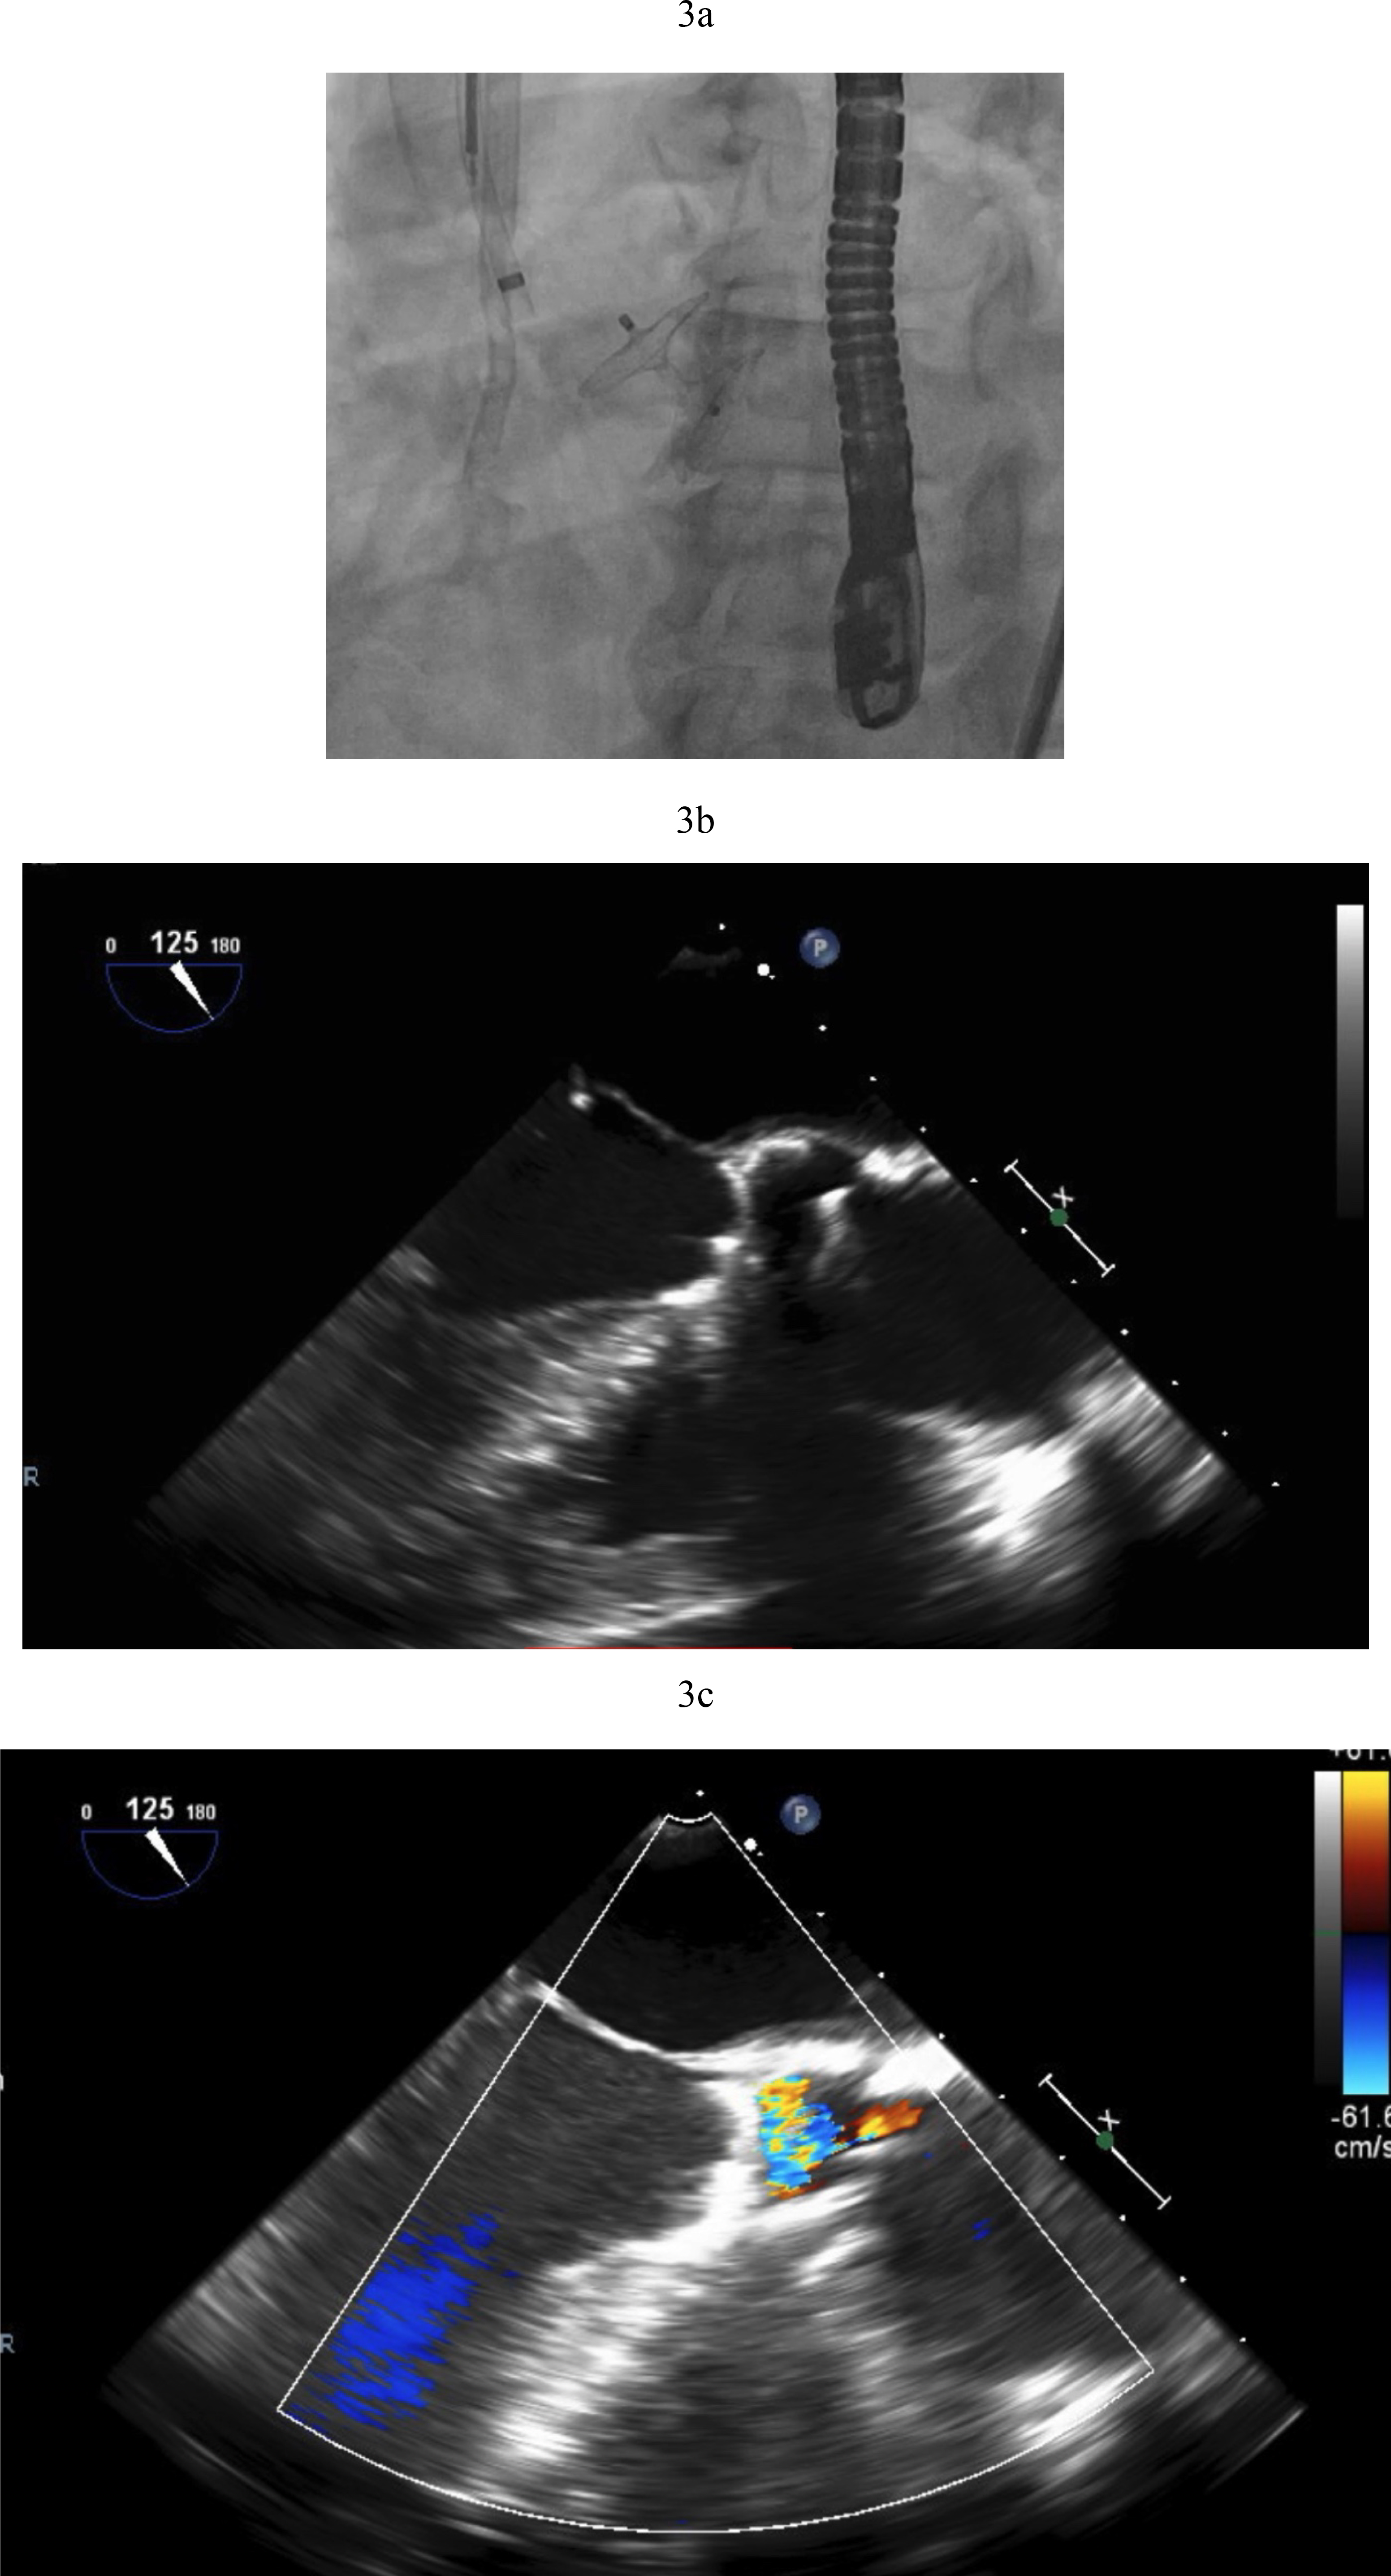

Transcatheter AV closure was first reported in 2011 using Amplatzer Septal Occluders (Abbott Structural, Minneapolis, MN, USA). However, while this is a relatively uncomplicated procedure, long term outcomes are not favorable. Mortality in small case series is high with poor long term survival of 30% at 6 months [15]. Hemolysis is expected for a period of days after deployment until the device is fully endothelialized (Fig. 3a–c).

Fig. 3. Amplatzer closure of aortic valve. (a) Amplatzer septal occluder across native aortic valve. (b) TEE showing the two discs of the Amplatzer device closing the aortic valve. (c) Aortic regurgitation resolved after Amplatzer closure. TEE, transesophageal echocardiogram.